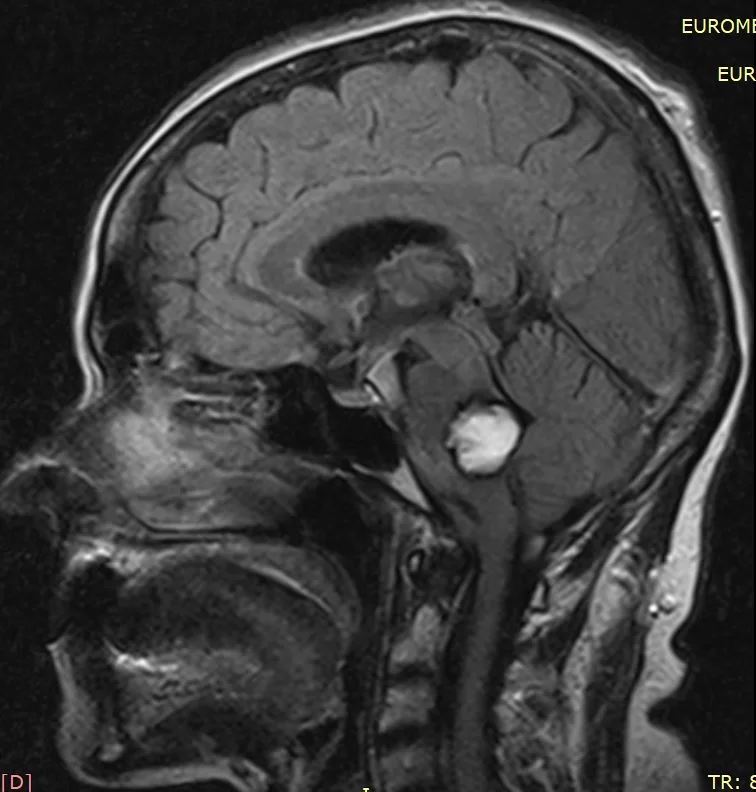

Τα σηραγγώδη αγγειώματα (ή αλλιώς καβερνώματα ή κρυπτικά αγγειώματα ή αιμαγγειώματα-αν και ο τελευταίος όρος είναι λάθος) είναι αγγειακές δυσπλασίες και συγκεκριμένα ένα συνοθύλευμα παθολογικών αγγείων στον εγκέφαλο και μερικές φορές και στο νωτιαίο μυελό (Εικόνα 1). Μοιάζει λίγο με «βατόμουρο» και είναι γεμάτο με αίμα το οποίο ρέει αργά στα αγγεία του. Το μέγεθος μπορεί να ποικίλει, από ελάχιστα χιλιοστά μέχρι μερικά εκατοστά.